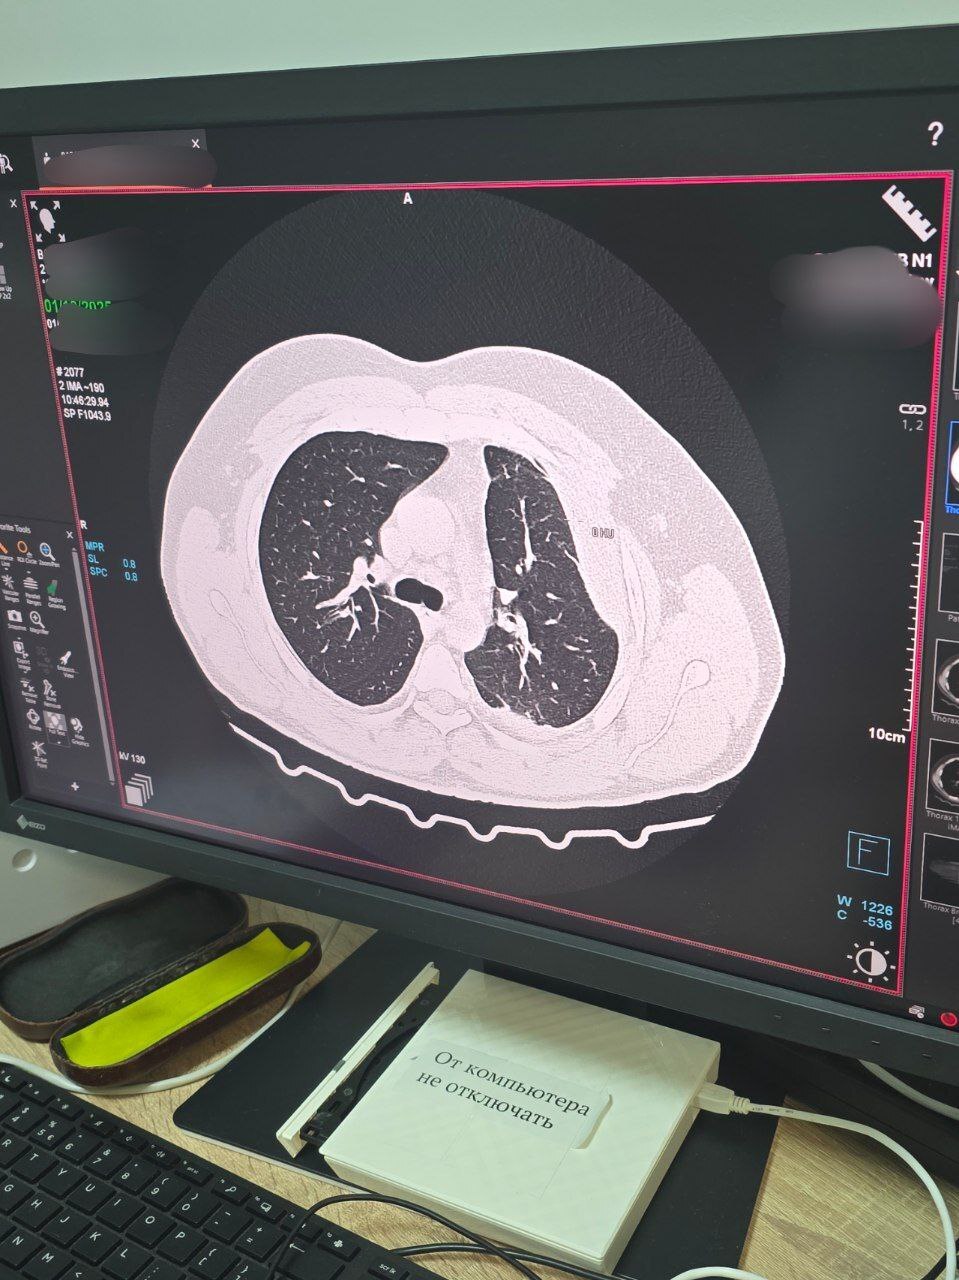

В рамках реализации программы модернизации первичного звена здравоохранения нацпроекта «Здравоохранение», инициированного Президентом РФ Владимиром Путиным приобретен компьютерный томограф SOMATOM go.Now.

«Оборудование делает качественную медицинскую помощь более доступной, в приборе реализованы инновационные разработки в области организации рабочих процессов и удобства использования, которые повышают эффективность исследования. Все это обеспечивает замечательные результаты диагностики», - рассказал главный врач больницы Аслан Юанов.